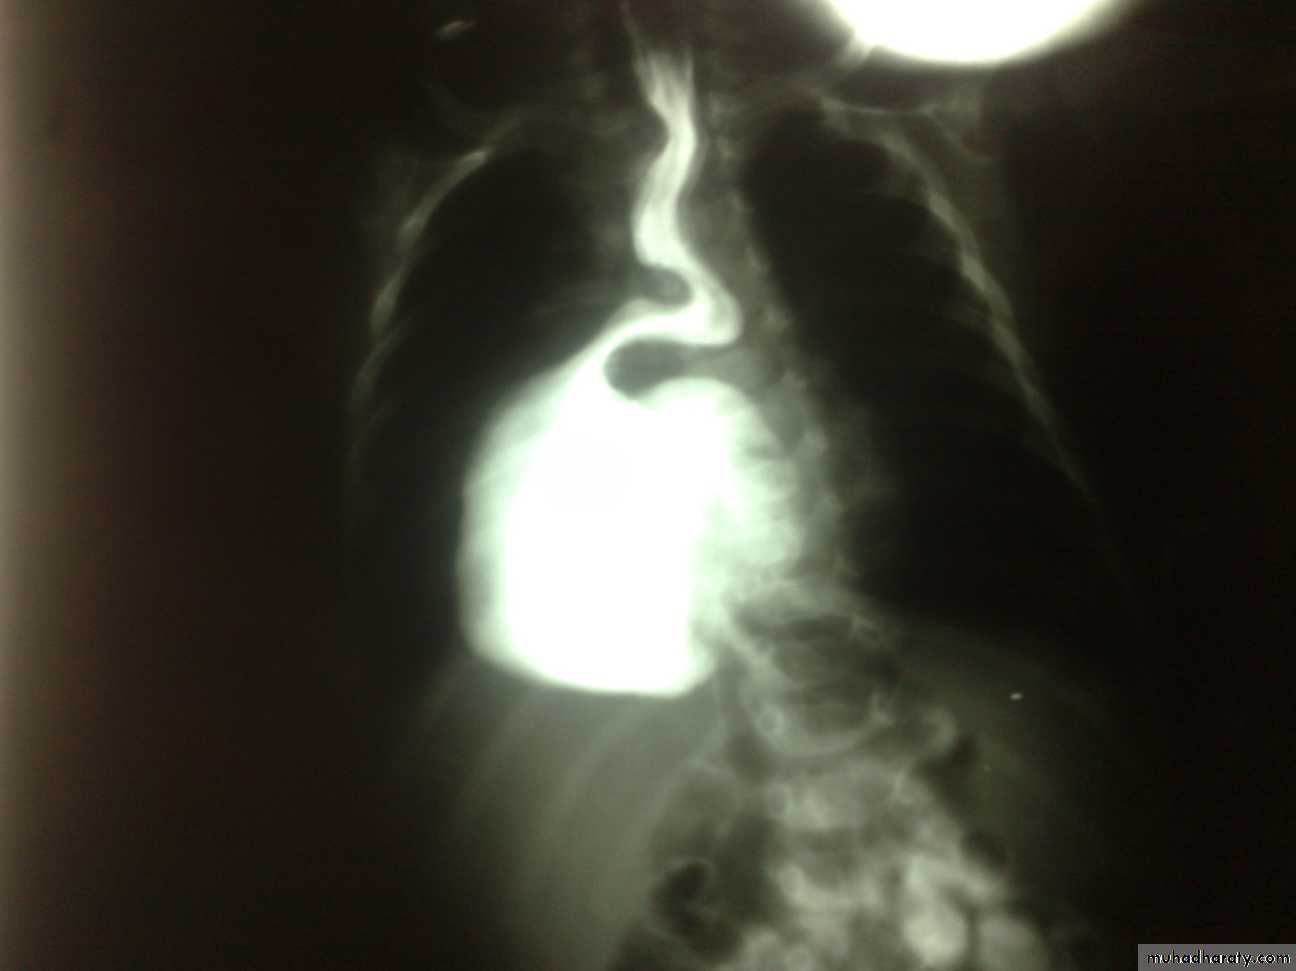

1 y.o infant with effortless vomiting since birth

Growth within normalDx:-Hiatus Hernia(above diaphragm)

Types:-sliding -Roling -Mixed(commonest in pediatrics)

*it’s associated with bleeding—often

-it’s subtype of D.H

Surgery:Fundiplication

surgery pyloromyotomy (rami stick surgery)Diagnosis: achalasia cardia

Ba-swallow dilatation of esophagus with narrowing of lower part.

Treatment cardiomyotomy +fundoplication(by abd. Approach)